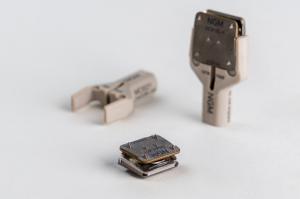

Spinal motion preservation is a significant focus for NGMedical. The only articulating viscoelastic cervical artificial disc MOVE®-C already sets new standards worldwide. NGMedical is driven by the goal to improve patients’ life with the most advanced solutions.

NGMedical pushes the limits of motion preserving spine treatment. Our focus lays on motion preserving technologies like the unique MOVE®-C and the advanced lumbar concept of MOVE®-P and is completed by state-of-the-art fusion products. Market changing developments made in Germany.